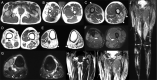

Segmental areas of denervation in post-polio syndrome